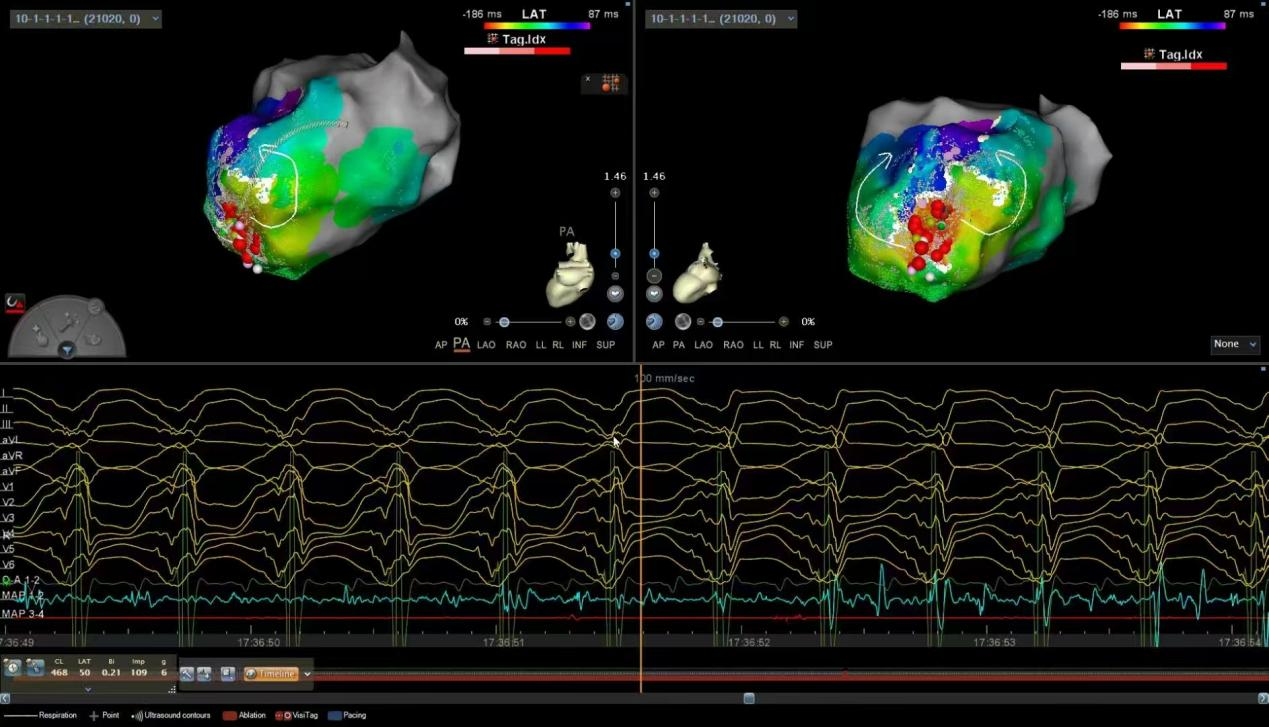

超高精密度标测指导下的器质性室速消融术

ü建立超高精密度标测指导室速消融新技术,累积完成3例国内超高难度器质性室速消融(其中两例为电风暴),术后无一例室速复发,提升疑难心律失常诊治水平!

ü心内、外科强强联合,内膜外膜联合标测消融,成功完成一例超大左室,主动脉瓣置换术后,反复室速发作,ICD反复放电,更换起搏器后又面临电池耗竭的重症患者。该患者心脏移植排队一年无望,射频消融为其重启生命动力。